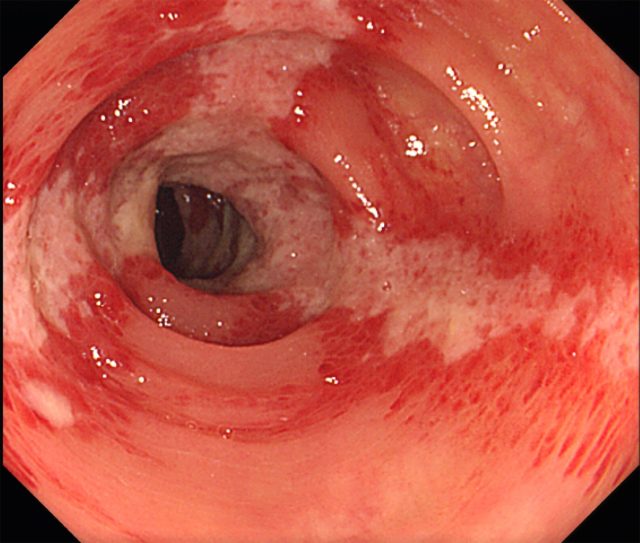

虚血性大腸炎

大腸の血流が一時的に低下することで炎症が起き、突然の腹痛や血便、下痢などを引き起こす病気です。主に高齢の女性に多いですが、若い人にも発症し、動脈硬化や便秘、脱水など様々な要因が関係します。

ほとんどのケースは一過性で自然に回復しますが、重症化して手術が必要になることもあります。